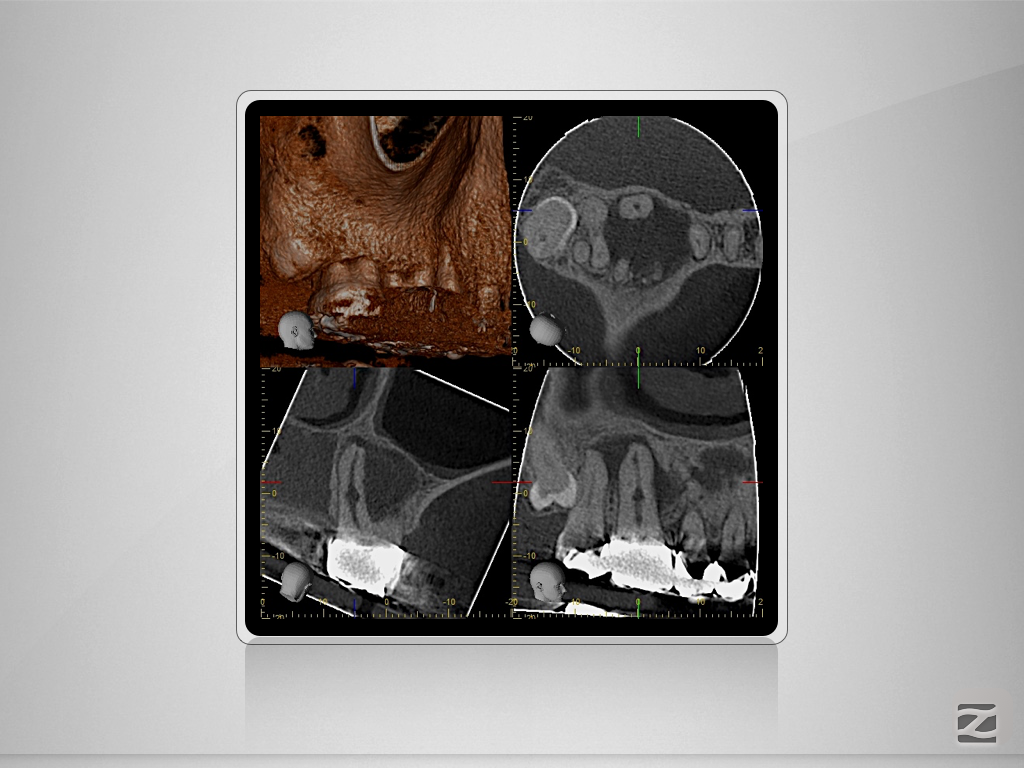

16D.003

Immer schön skeptisch bleiben 4